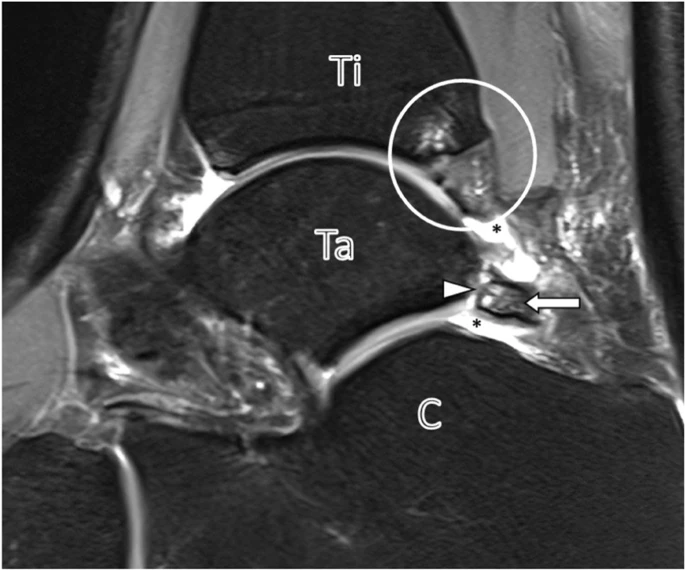

诊断